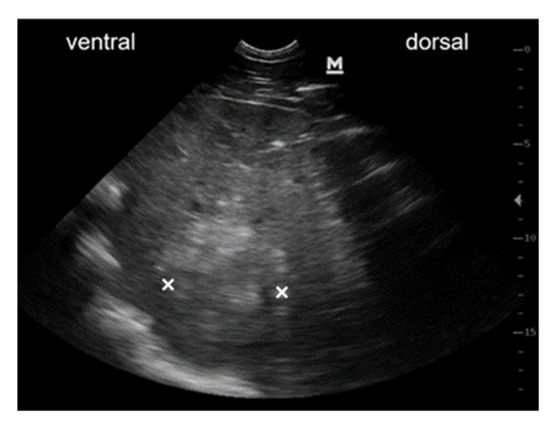

3.3.1. Case #1

3.3.2. Case #2